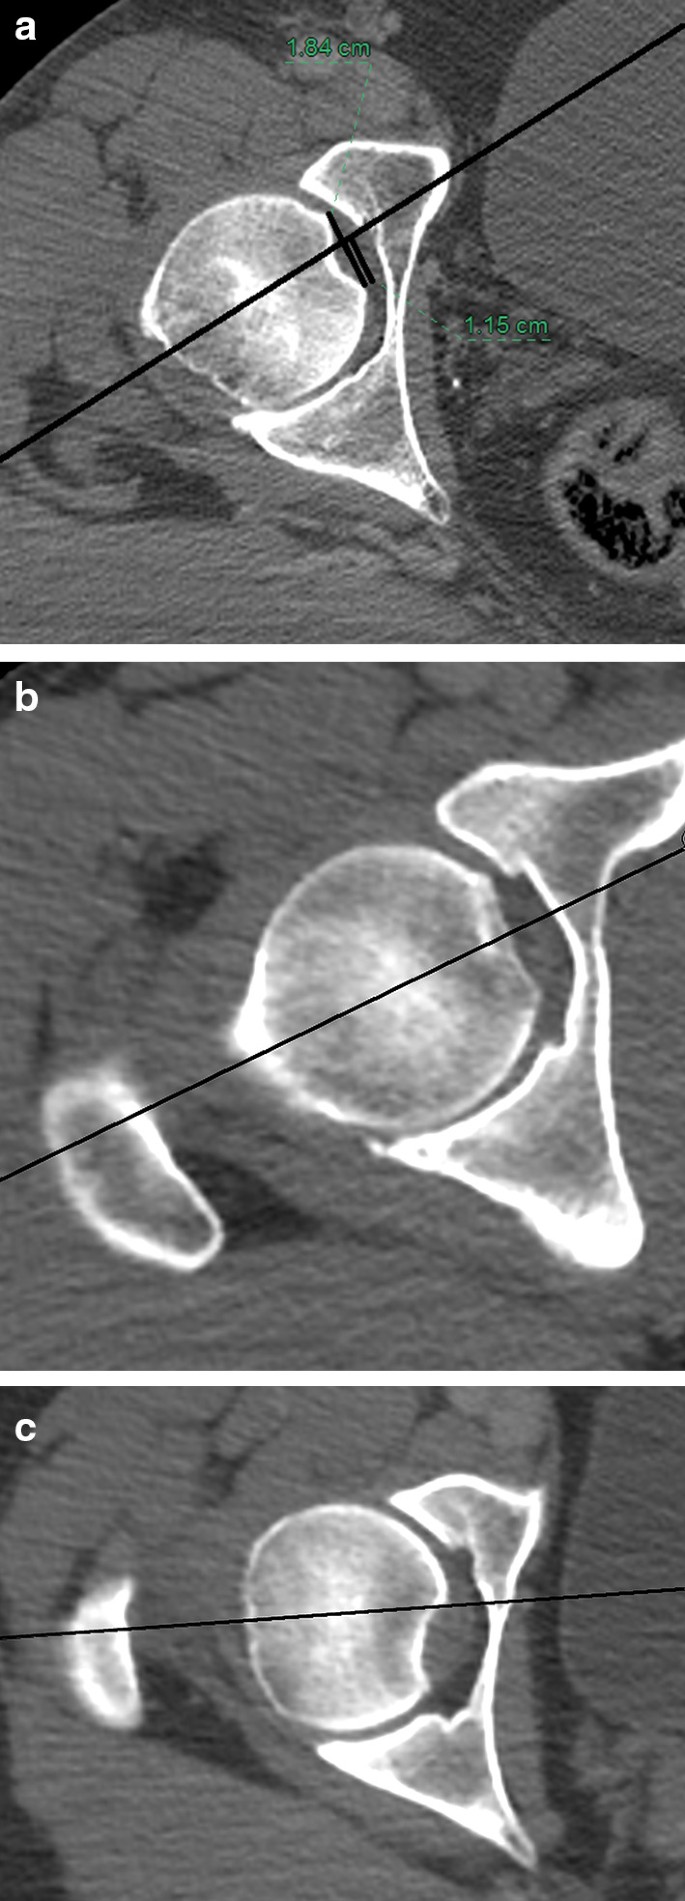

In the transverse plane, the axis crossed the fovea in every case in the anterior half of the fovea; therefore, always, half or more of the fovea diameter was posterior to the axis (Fig. 5a). As shown in Table 1, approximately ¾ of the fovea diameter in the transverse plane is located posterior to the neck axis. This number is always between 50 and 100%. However, the axis never passed outside the fovea. Only in some cases, the axis was directly central in the fovea or at the anterior border (Fig. 5b, c).

Fig. 5

figure 5

Location of the fovea in relation with the femoral neck axis in the transverse view. a Posterocentral. b Central. c Posterior